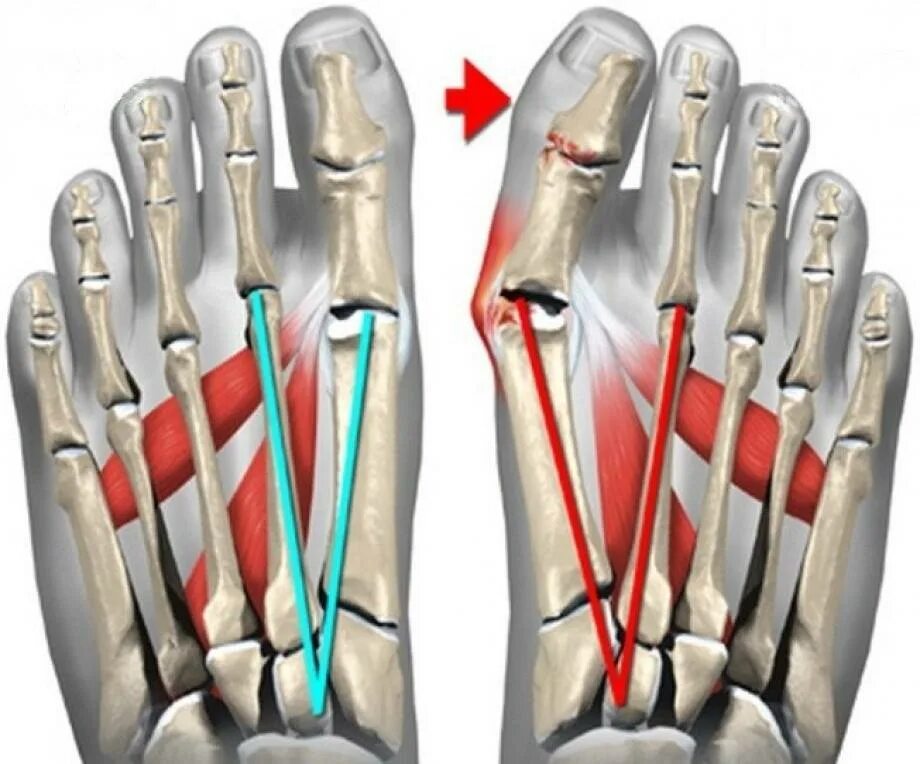

Операция деформации пальцев стопы